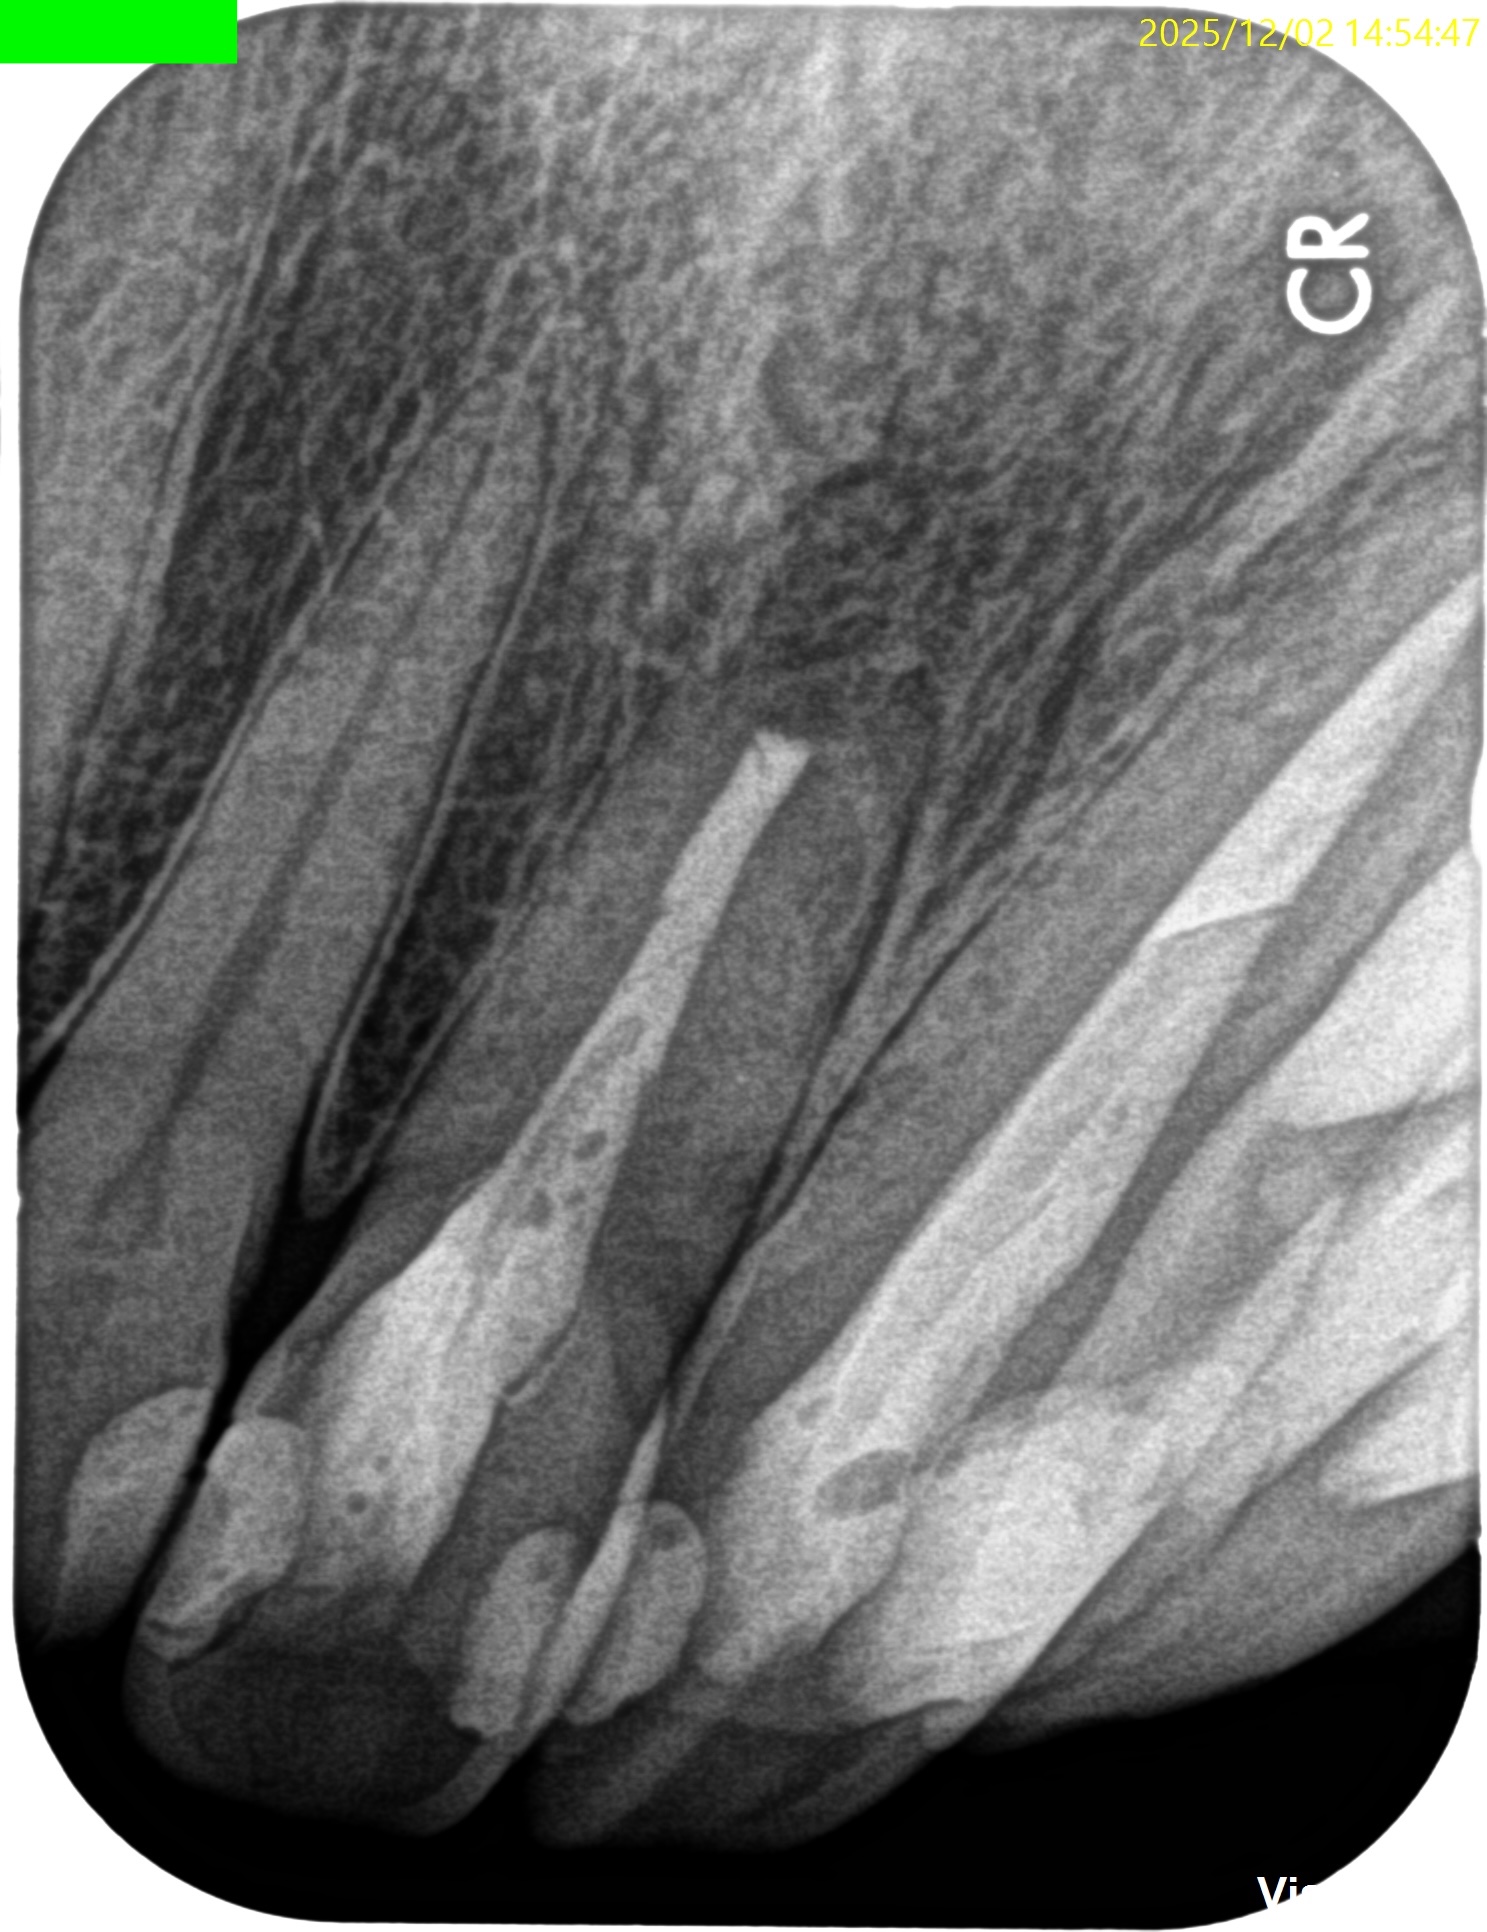

PA(2025.6.3)

#8,9,10ともに全く根管治療が不適切としか言いようがない。

#8はForamen付近の形成が太そうだ。

#8 Apicoectomy 6M recall(2025.12.2)

PA, CBCTを撮影した。

初診時と比較した。

劇的に状況は改善している。